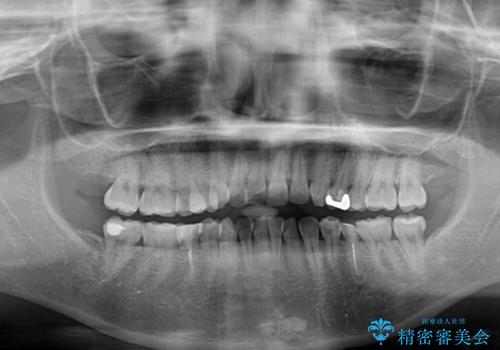

開咬と前方に飛び出した前歯 インビザラインによる矯正治療

- 上下前歯の非接触と叢生を気にして来院された患者様です。

開咬の改善はインビザラインの最も得意とするところであるため、インビザラインを用いて矯正治療を行うこととしました。